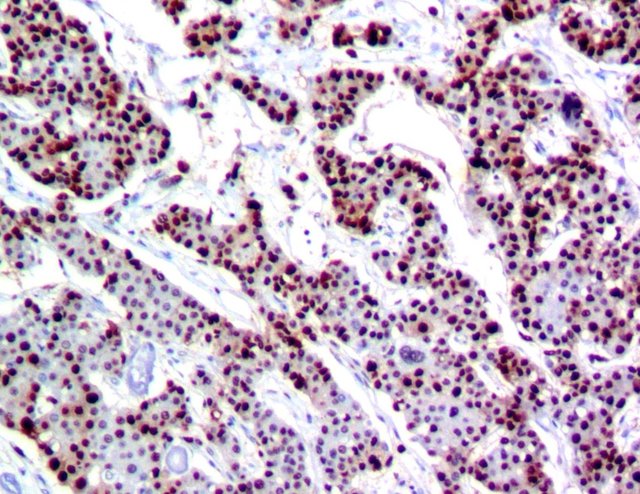

下图分别为细胞浆阳性表达,细胞核阳性表达,细胞膜阳性表达